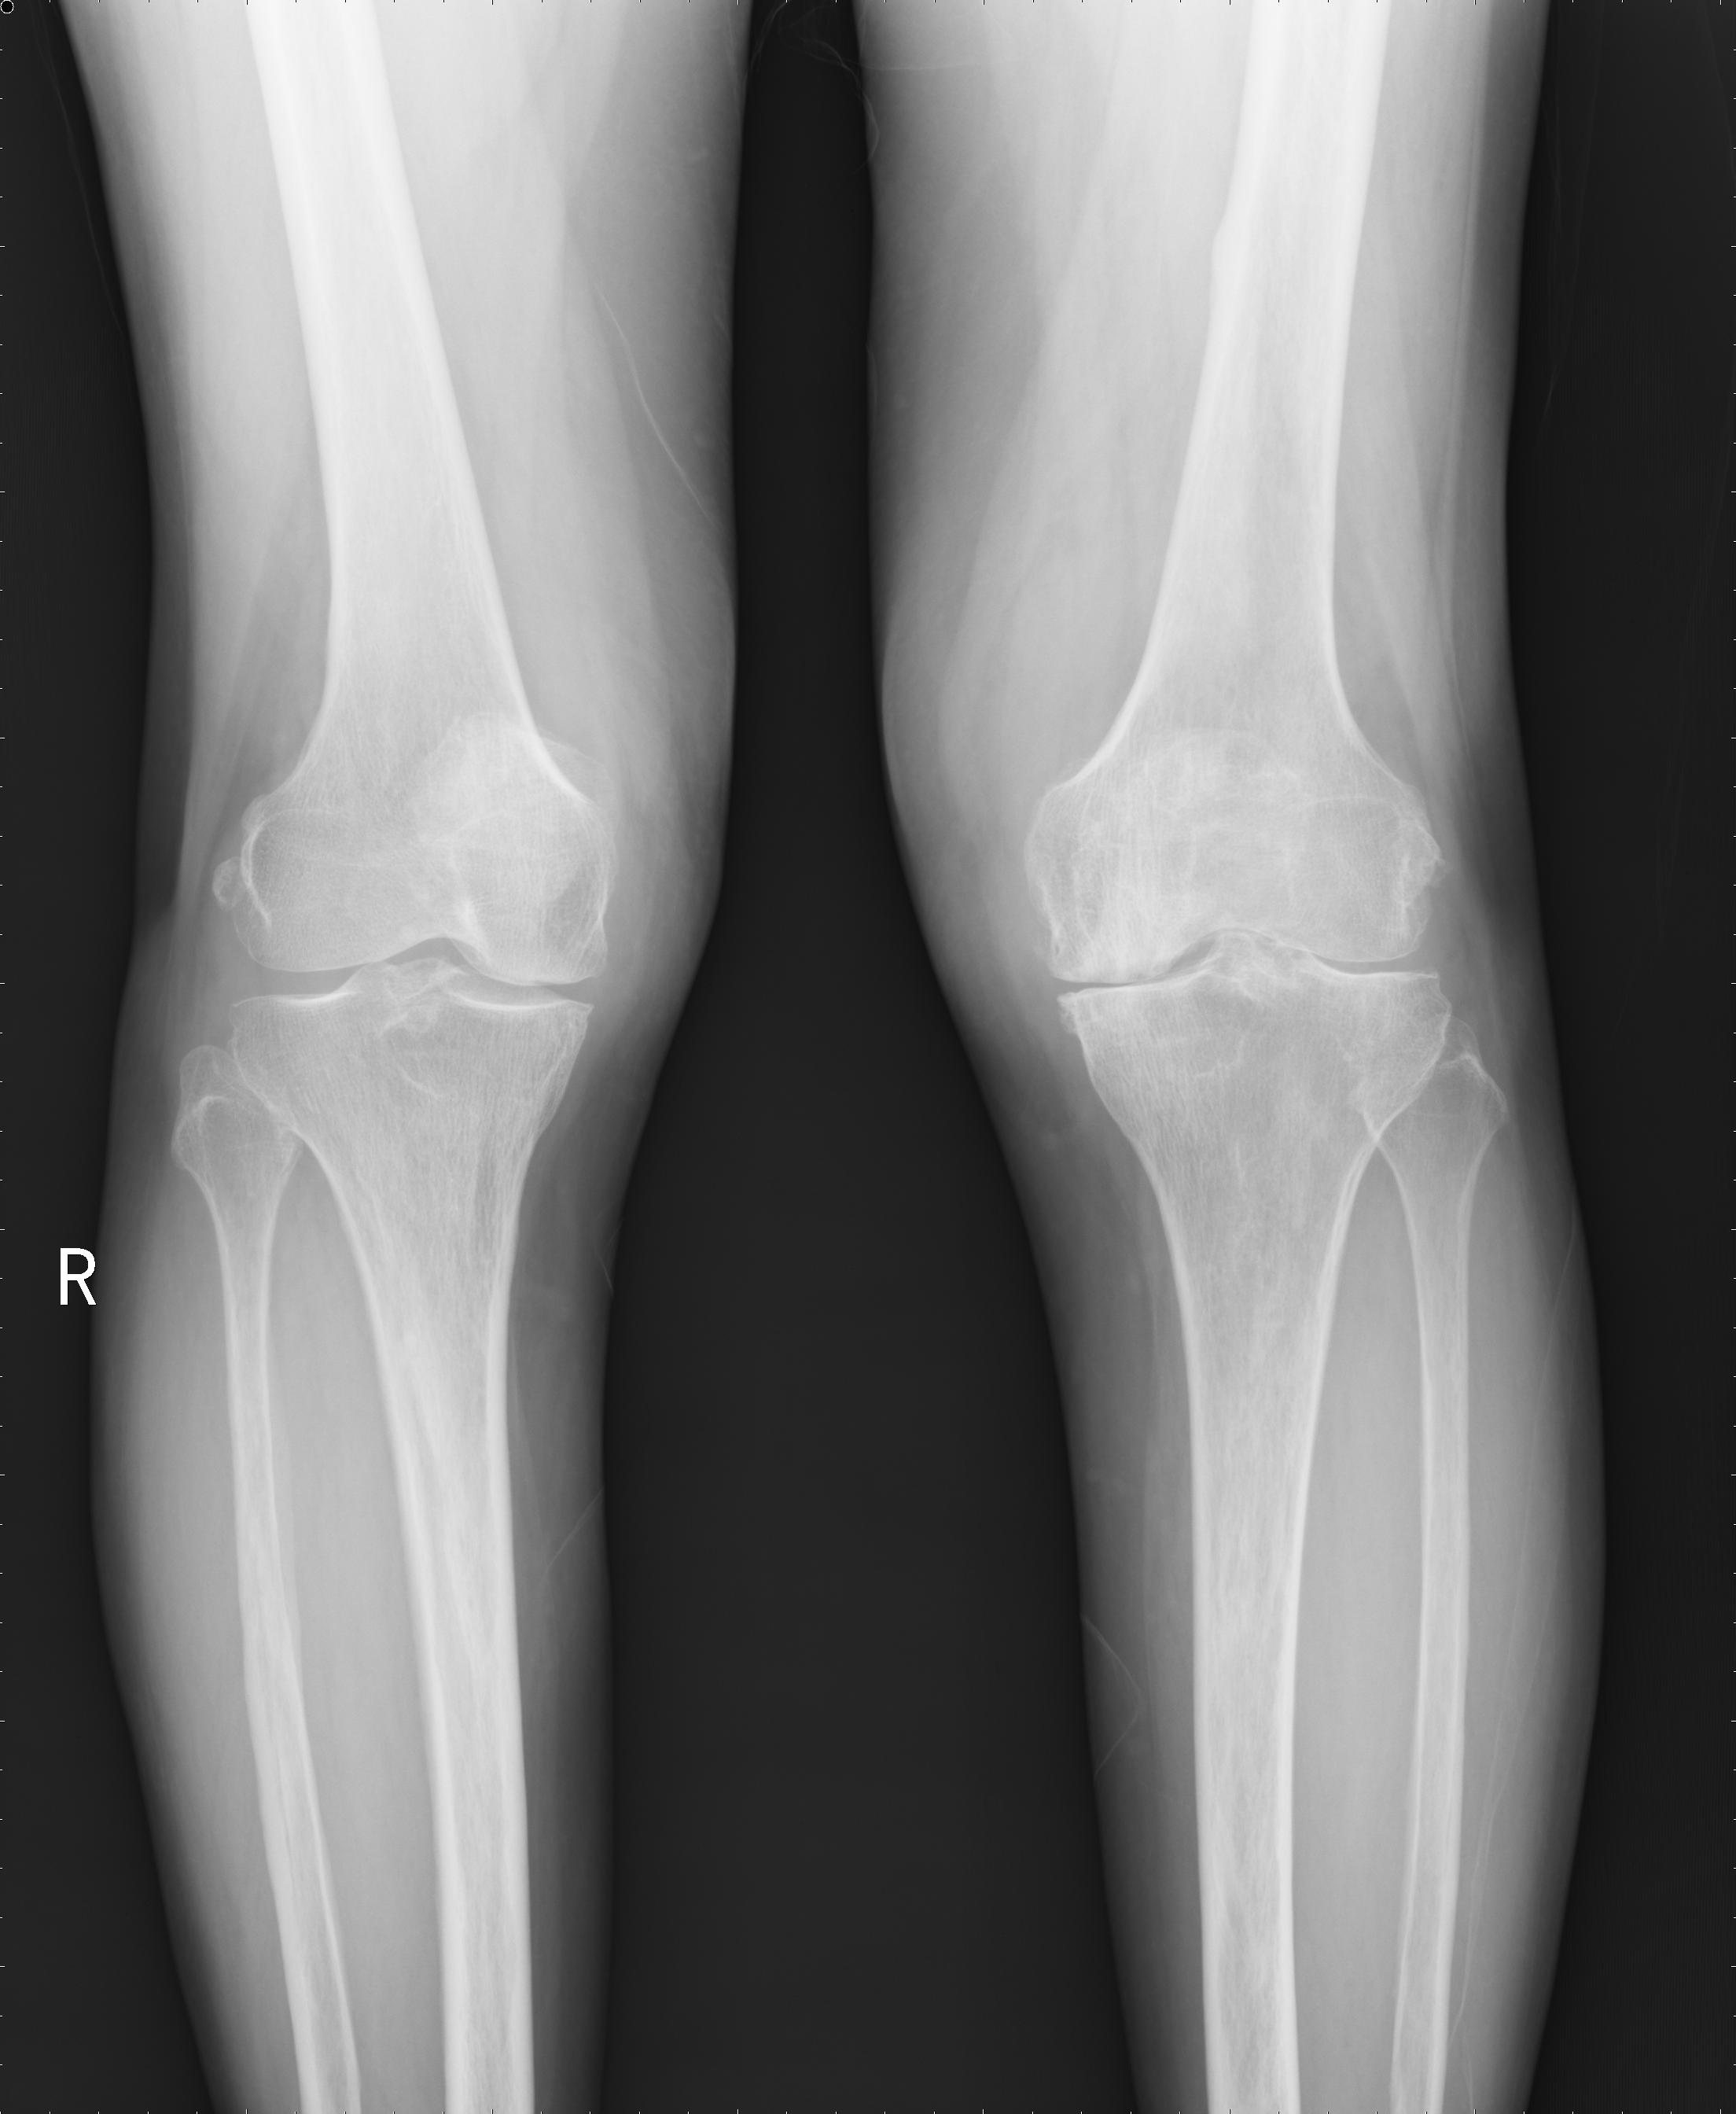

病例三:患者女性,66歲。主因“右膝疼痛4年多”入院。入院前患者有4年多時(shí)間不能正常行走,每次下地需扶墻行走,每次只行走幾米遠(yuǎn)。

患者術(shù)前

患者術(shù)后

患者術(shù)后全長